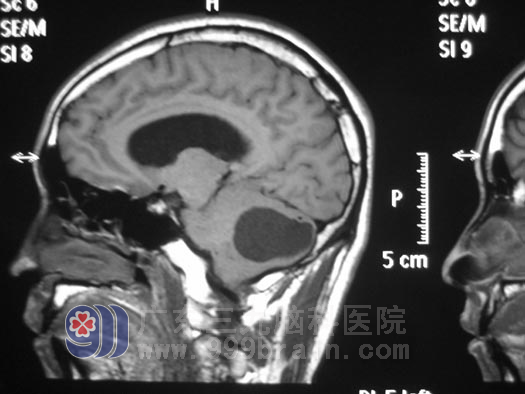

手术前

入院诊断为:左侧小脑占位、梗阻性脑积水、小脑扁桃体下疝畸形,并于 10月27日,由鲁明 主任主刀,为叶先生实施了左侧小脑占位切除+小脑扁桃体部分切除+寰椎减压+颅内压探头置入术。手术全程约6小时,术程顺利,手术成功。

据神经外五科 鲁明 主任介绍,此次手术为叶先生一下子解决了左侧小脑占位、梗阻性脑积水、小脑扁桃体下疝畸形三个问题。为了避免术后小脑创面水肿,小脑体积增大,出现小脑扁桃体下疝,避免术后再次出现小脑扁桃体下疝压迫延髓而威胁生命,鲁明 主任为叶先生实施了寰椎减压术;并于手术中行颅内压探头置入术,以便捷地了解手术后颅内压力的变化,术后复查MR显示占位全切,术后病理回报为:左侧小脑半球血管母细胞瘤。www.999brain.com